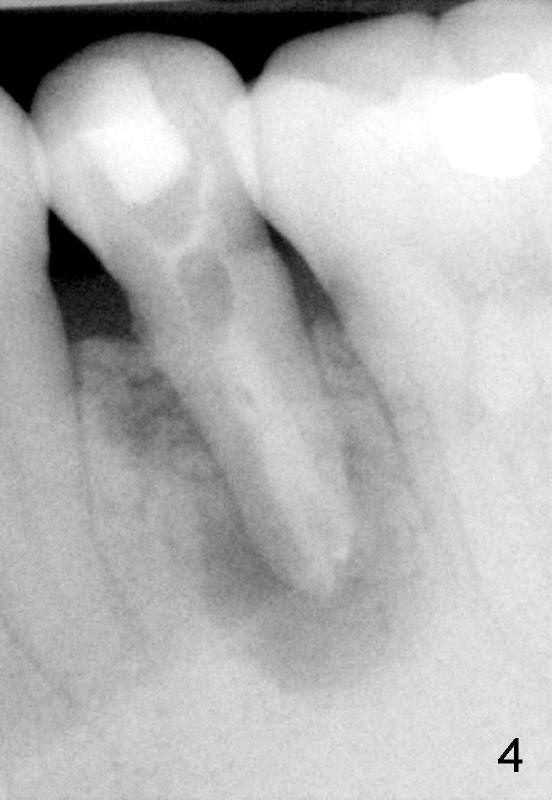

A 40-year-old Chinese man has periodic (once a month) mild pain and swelling in the lower left quadrant. Clinical exam reveals dens evaginatus (Fgi.1': <) in #20. Upon pressure from mouth mirror handle, there is limited amount of purulent discharge from the fistula (Fig.1": <). Preop PA shows a large canal with large periapical radiolucency (Fig.1). RCT started on Aug 6, 2010 with #70 file at 20 mm (Fig.2), #120 file at 16 mm (Fig.3) and CaOH paste in the canal (Fig.4). The dressing changed on Oct 8, 2010 (Fig.5). RCT finished on Jan 25, 2011 with master cone (rolled with several gutta perchae) (Fig.6), lateral condensation (Fig.7) and after vertical condensation and build-up (Fig.8). The canal was wet in the last two appointments with no sign of apexification. Follow up is done in 7 months (Fig.9), 11 months (Fig.10) and 18 months. Although the patient reports no pain after the treatment, the fistula remains with purulent discharge. The patient does not accept apical surgery. What should we do? Retreat with MTA (1,2,3)?